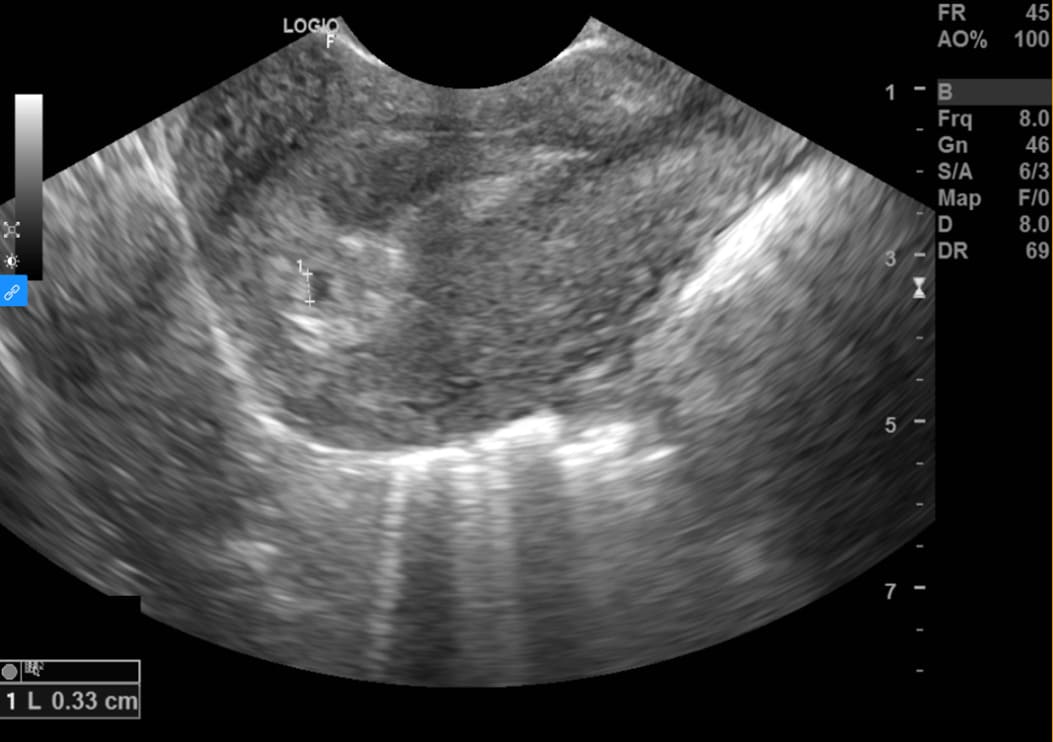

Là loại siêu âm sử dụng loại đầu dò đặc biệt (nhỏ và dài) để đưa vào trong âm đạo, nhằm quan sát rõ nhất các cấu trúc của tử cung – phần phụ, vì đầu dò được đưa vào sát cổ tử cung. Đây là kĩ thuật được ưu tiên trong đánh giá và chẩn đoán thai nhỏ, vì kích thước thai nhỏ, cần một kĩ thuật có độ phân giải cao.

Kĩ thuật có thể được thực hiện từ khi người phụ nữ có dấu hiệu chậm kinh, đến khi thai 12 tuần tuổi, giúp đánh giá xem thai đã vào buồng tử cung hay chưa, số lượng thai là bao nhiêu, có tim thai chưa và tần số tim thai như thế nào, đo kích thước phôi thai để đưa ra dự kiến sinh; ngoài ra siêu âm đầu dò còn đánh giá được tình trạng bánh rau, dây rốn, túi thai, hay các bất thường như tụ dịch – tụ máu dưới màng nuôi, dọa sảy thai, thai ngoài tử cung… Từ đó, các bác sĩ có thể chẩn đoán và xử trí kịp thời cho sản phụ, tránh các biến chứng nguy hiểm.

Siêu âm thai bằng đầu dò âm đạo có thể phát hiện được túi thai khi kích thước còn rất nhỏ